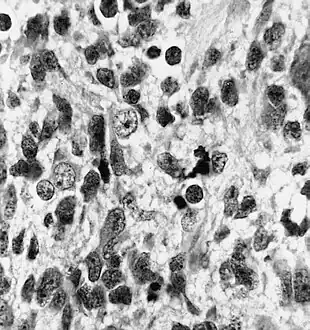

| Histopathology of medulloepithelioma showing characteristic neural tube like strands. | |

Histologically, medulloepithelioma resemble a primitive neural tube and with neuronal, glial and mesenchymal elements.[8][9] Flexner-Wintersteiner rosettes may also be observed.[10]